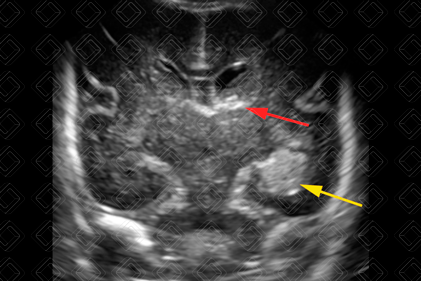

Descrição das figuras 1 e 2: Ultrassonografia transfontanela; imagens coronal e parassagitais direita e esquerda evidenciando áreas triangulares hiperecogênicas (setas vermelhas) na topografia dos sulcos caudotalâmicos bilateralmente, compatível com hemorragia de matriz germinativa grau I bilateral.

• Grau I: Hemorragia presente somente no sulco caudotalâmico (figuras 1 e 2);